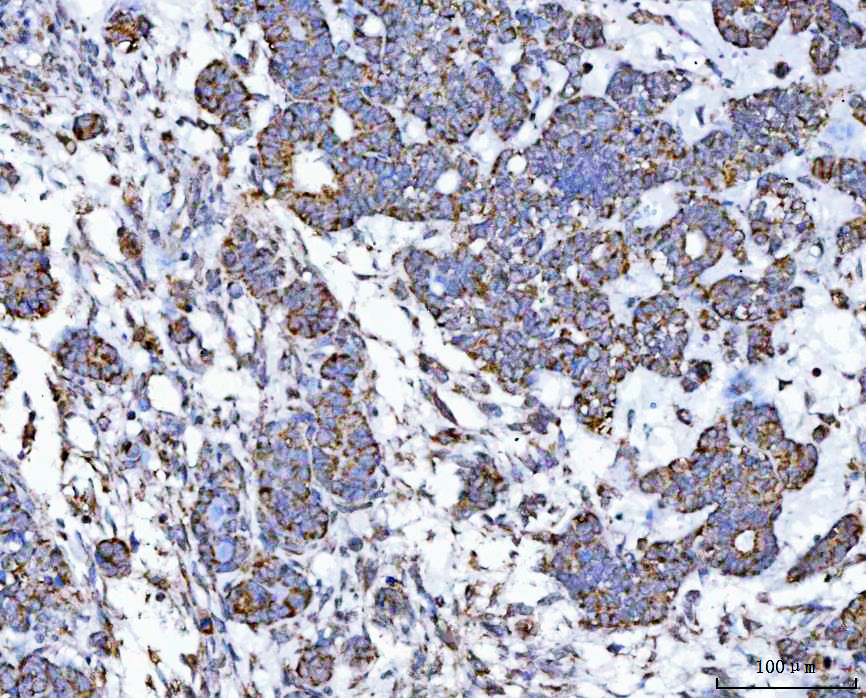

IHC analysis of VDAC1 using anti-VDAC1 antibody (BA3754).

VDAC1 was detected in a paraffin-embedded section of human lung cancer tissue. The tissue section was developed using HRP Conjugated Rabbit IgG Super Vision Assay Kit (Catalog # SV0002) with DAB (Catalog # AR1027) as the chromogen.